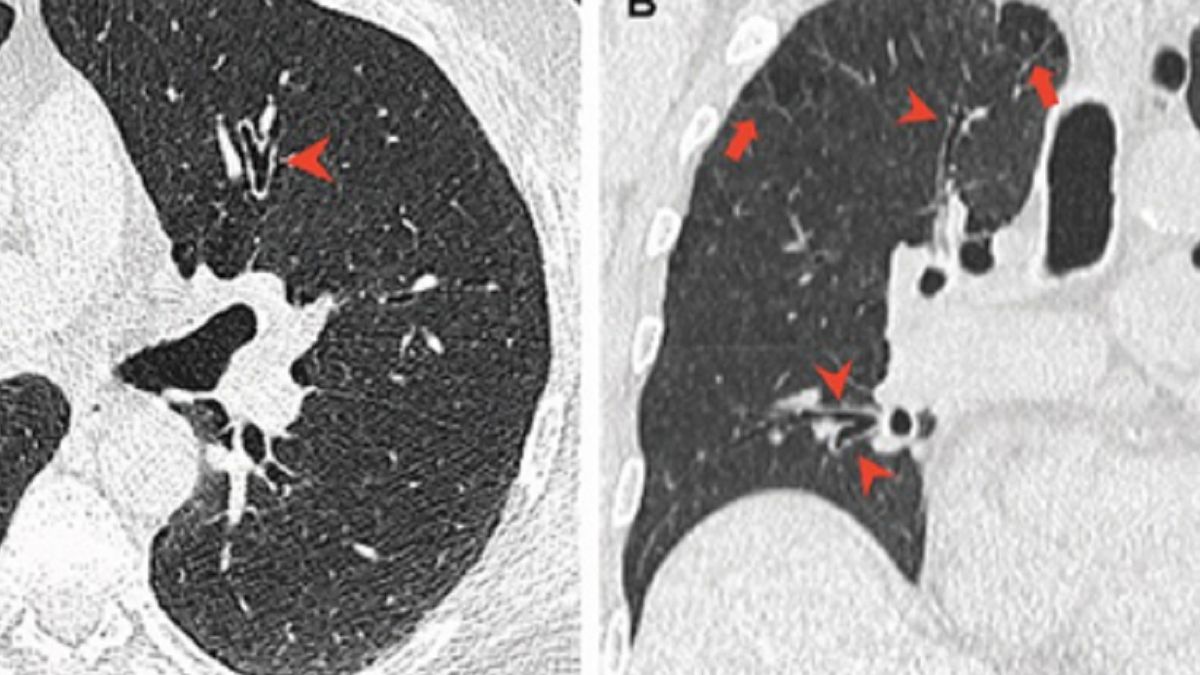

Konopie indyjskie mogą wyrządzić więcej szkód płucom i drogom oddechowych palacza niż tytoń. Tak wynika z kanadyjskiego badania opublikowanego we wtorek przez naukowców w Ottawie.

Nad szkodliwym wpływem palenia marihuany na płuca zastanawiał się prawdopodobnie każdy regularny konsument konopi. Czy lecznicze właściwości rośliny mogą rekompensować szkodliwość powstających w procesie spalania związków? Nad tym tematem pochylili się naukowcy z University of Ottawa i szpitala w Ottawie.

Wszyscy przyjrzeli się skanom rentgenowskim klatki piersiowej 56 palaczy konopi indyjskich, 57 skanom osób niepalących i wynikom 33 osób, które paliły tylko tytoń w latach 2005-2020.

Zarówno palacze tytoniu, jak i marihuany, mają nadmiernie napompowane płuca, jednak palacze marihuany mają średnio większą objętość płuc i niższe tempo transferu gazu. Oznacza to, że palacze marihuany są narażeni na komplikacje płucne, zwłaszcza, jeśli palą oni również tytoń.

Lekarze stwierdzili, że wskaźniki zapalenia dróg oddechowych i rozedmy płuc, czyli przewlekłej choroby, są wyższe wśród regularnych palaczy konopi, niż u osób, które palą tytoń lub całkowicie odrzucają marihuanę oraz tytoń.

Marihuana jest palona niefiltrowana, w przeciwieństwie do tytoniu, który jest zwykle filtrowany - powiedziała radiolog. - Kiedy palisz niefiltrowaną marihuanę, więcej cząsteczek dociera do dróg oddechowych, osadza się tam i podrażnia drogi oddechowe - wyjaśnia.